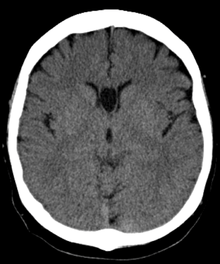

The cave of septum pellucidum (CSP) describes a septum pellucidum that has a separation between its two leaflets (septal laminae). This cavity contains cerebrospinal fluid (CSF) that filters from the ventricles through the septal laminae.[1]

The cave of septum pellucidum is bounded anteriorly by the genu of the corpus callosum; superiorly by the body of the corpus callosum; posteriorly by the anterior limb and pillars of the fornix; inferiorly by the anterior commissure and the rostrum of the corpus callosum; and laterally by the leaflets of the septum pellucidum.[2]

There are individual differences in the degree of CSP; whereas some have complete closure of the cavum, others present with a small degree (4-6mm in the coronal plane) of incomplete closure.[3]

The most common type of CSP is noncommunicating, that is, it does not connect to the brain's ventricular system. Because of this lack of communication, the erstwhile term for CSP, the "fifth ventricle," is not anatomically correct and its use has fallen out of favor in recent years.